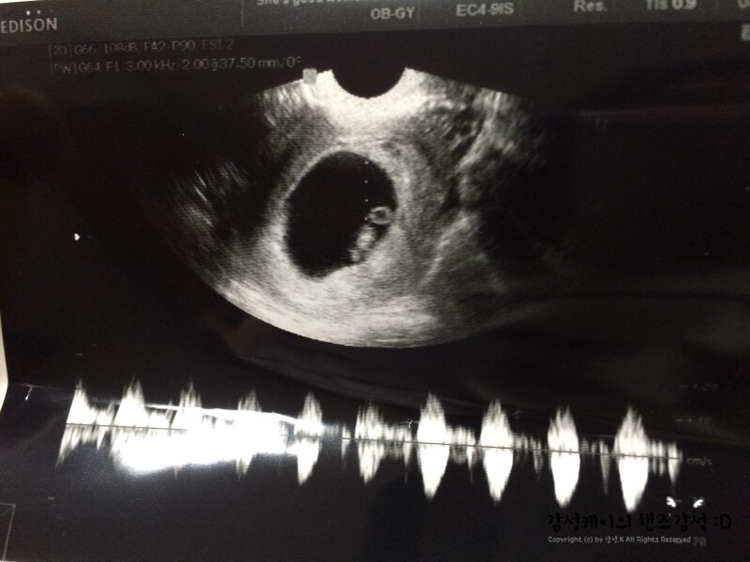

하지만 정말... 다행히도.... 정말 고맙게도.... 텅 비어있던 아기집엔 작은 무언가가 하나 생겨나 있었고 나는 그날 처음 아이의 심장소리도 들을 수 있었다. 아이가 잘 있네요 라는 의사 선생님의 말과 함께 말이다. 어찌나 눈물이 나던지... 난 그때 아이를 위해서라도 앞으로 스트레스받지 않게 노력해야겠단 생각을 했다.

그런데 다행히 아이의 심장소리는 전 보다 더 건강하게 뛰고 있다고 의사 선생님께서 말씀해주셨다.

그리고 그새 팔도 생기고 다리도 생기고 주먹을 딱 쥐고 있는 모습 또한 초음파를 통해 보이는데 너무 귀여워서 나는 몇 번이고 보고 또 봤는지 모르겠다. 산부인과 선생님께서도 아기가 잘 크고 있다며 귀엽다고 말씀해주셨다. 엄마가 되는 길. 결코 쉽진 않진만 정말 노력해야겠다는 생각이 아이의 심장소리를 듣자마자 또 한번 다짐하게 되었다.